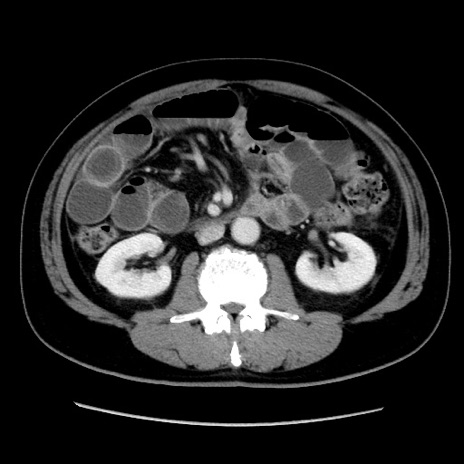

症例16(横断像)

【症例】 70歳代男性

【主訴】 腹痛、嘔吐

【現病歴】 約1ヶ月前より間欠的に腹痛と嘔吐あり、当院消化器内科を受診したところCTで多発する肝臓のLDAを指摘され、精査中であった。以降は消化器症状は安定していたが、2日前より嘔気と腹痛があり、同日より排便・排ガスが消失した。改善認めず、 本日、救急外来を受診した。

【既往歴】 大腸ポリープ切除後。

【身体所見】意識清明・会話良好、BT 36.3℃、BP 127/80mmHg、 P 80bpm、腹部:膨満あり、平坦・軟、上腹部正中および下腹部正中に圧痛あり、反跳痛なし、筋性防御なし。

【データ】WBC 7200、CRP 0.77